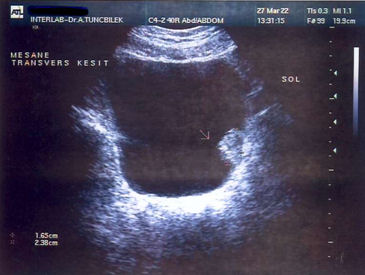

Intravenous urography (IVP) is a test which is frequently used to identify the hematuria. In IVP, the papillamatous formation extending into the bladder shows itself as a filling defect. Abdominal ultrasonography (US), Computed tomography (CT) and Magnetic Resonance (MRI) tests also show the occupying lesion within the bladder.